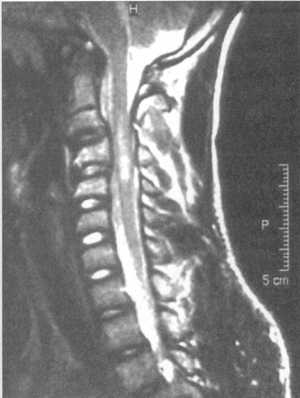

Ценную информацию о состоянии вывихнутых позвонков и спинного мозга дает

МРТ (рис. 2.6, 2.7). МРТ позволяет определить наличие зон ишемии в спинном

мозге (рис. 2.8, 2.9), состояние ликвородинамики (рис. 2.10).

Рис. 2.7. Переломо-вывих скользящий C6-C7 позвонков с компрессией

спинного мозга на данном уровне